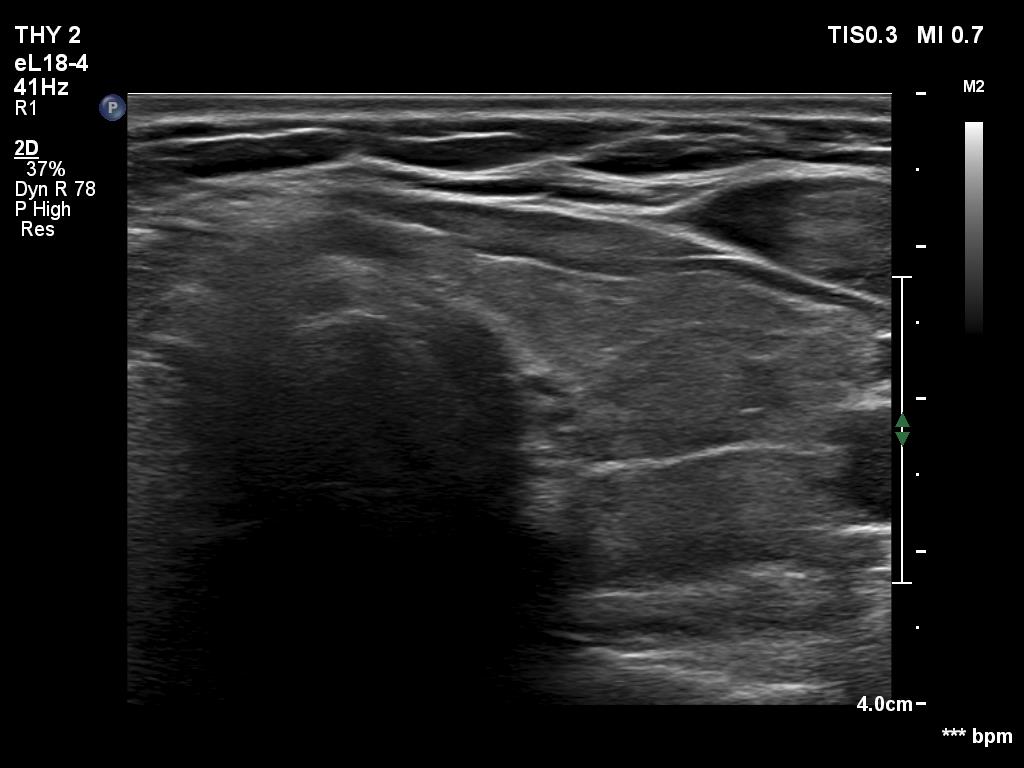

Second examination seven years later (second row of images):

Ultrasonography. The pattern and the thyroid volume were essentially the same as 7 years ago.Suggestion: daily 75 microgram levothyroxine. TSH in 6 months, ultrasound in three years.

The micronodular pattern is usually stable. The thyroid is more often enlarged than in other forms of hypothyroidism.

- As in most cases of micronodular presentation, the presence of true nodule or nodules cannot be ruled out or justified.